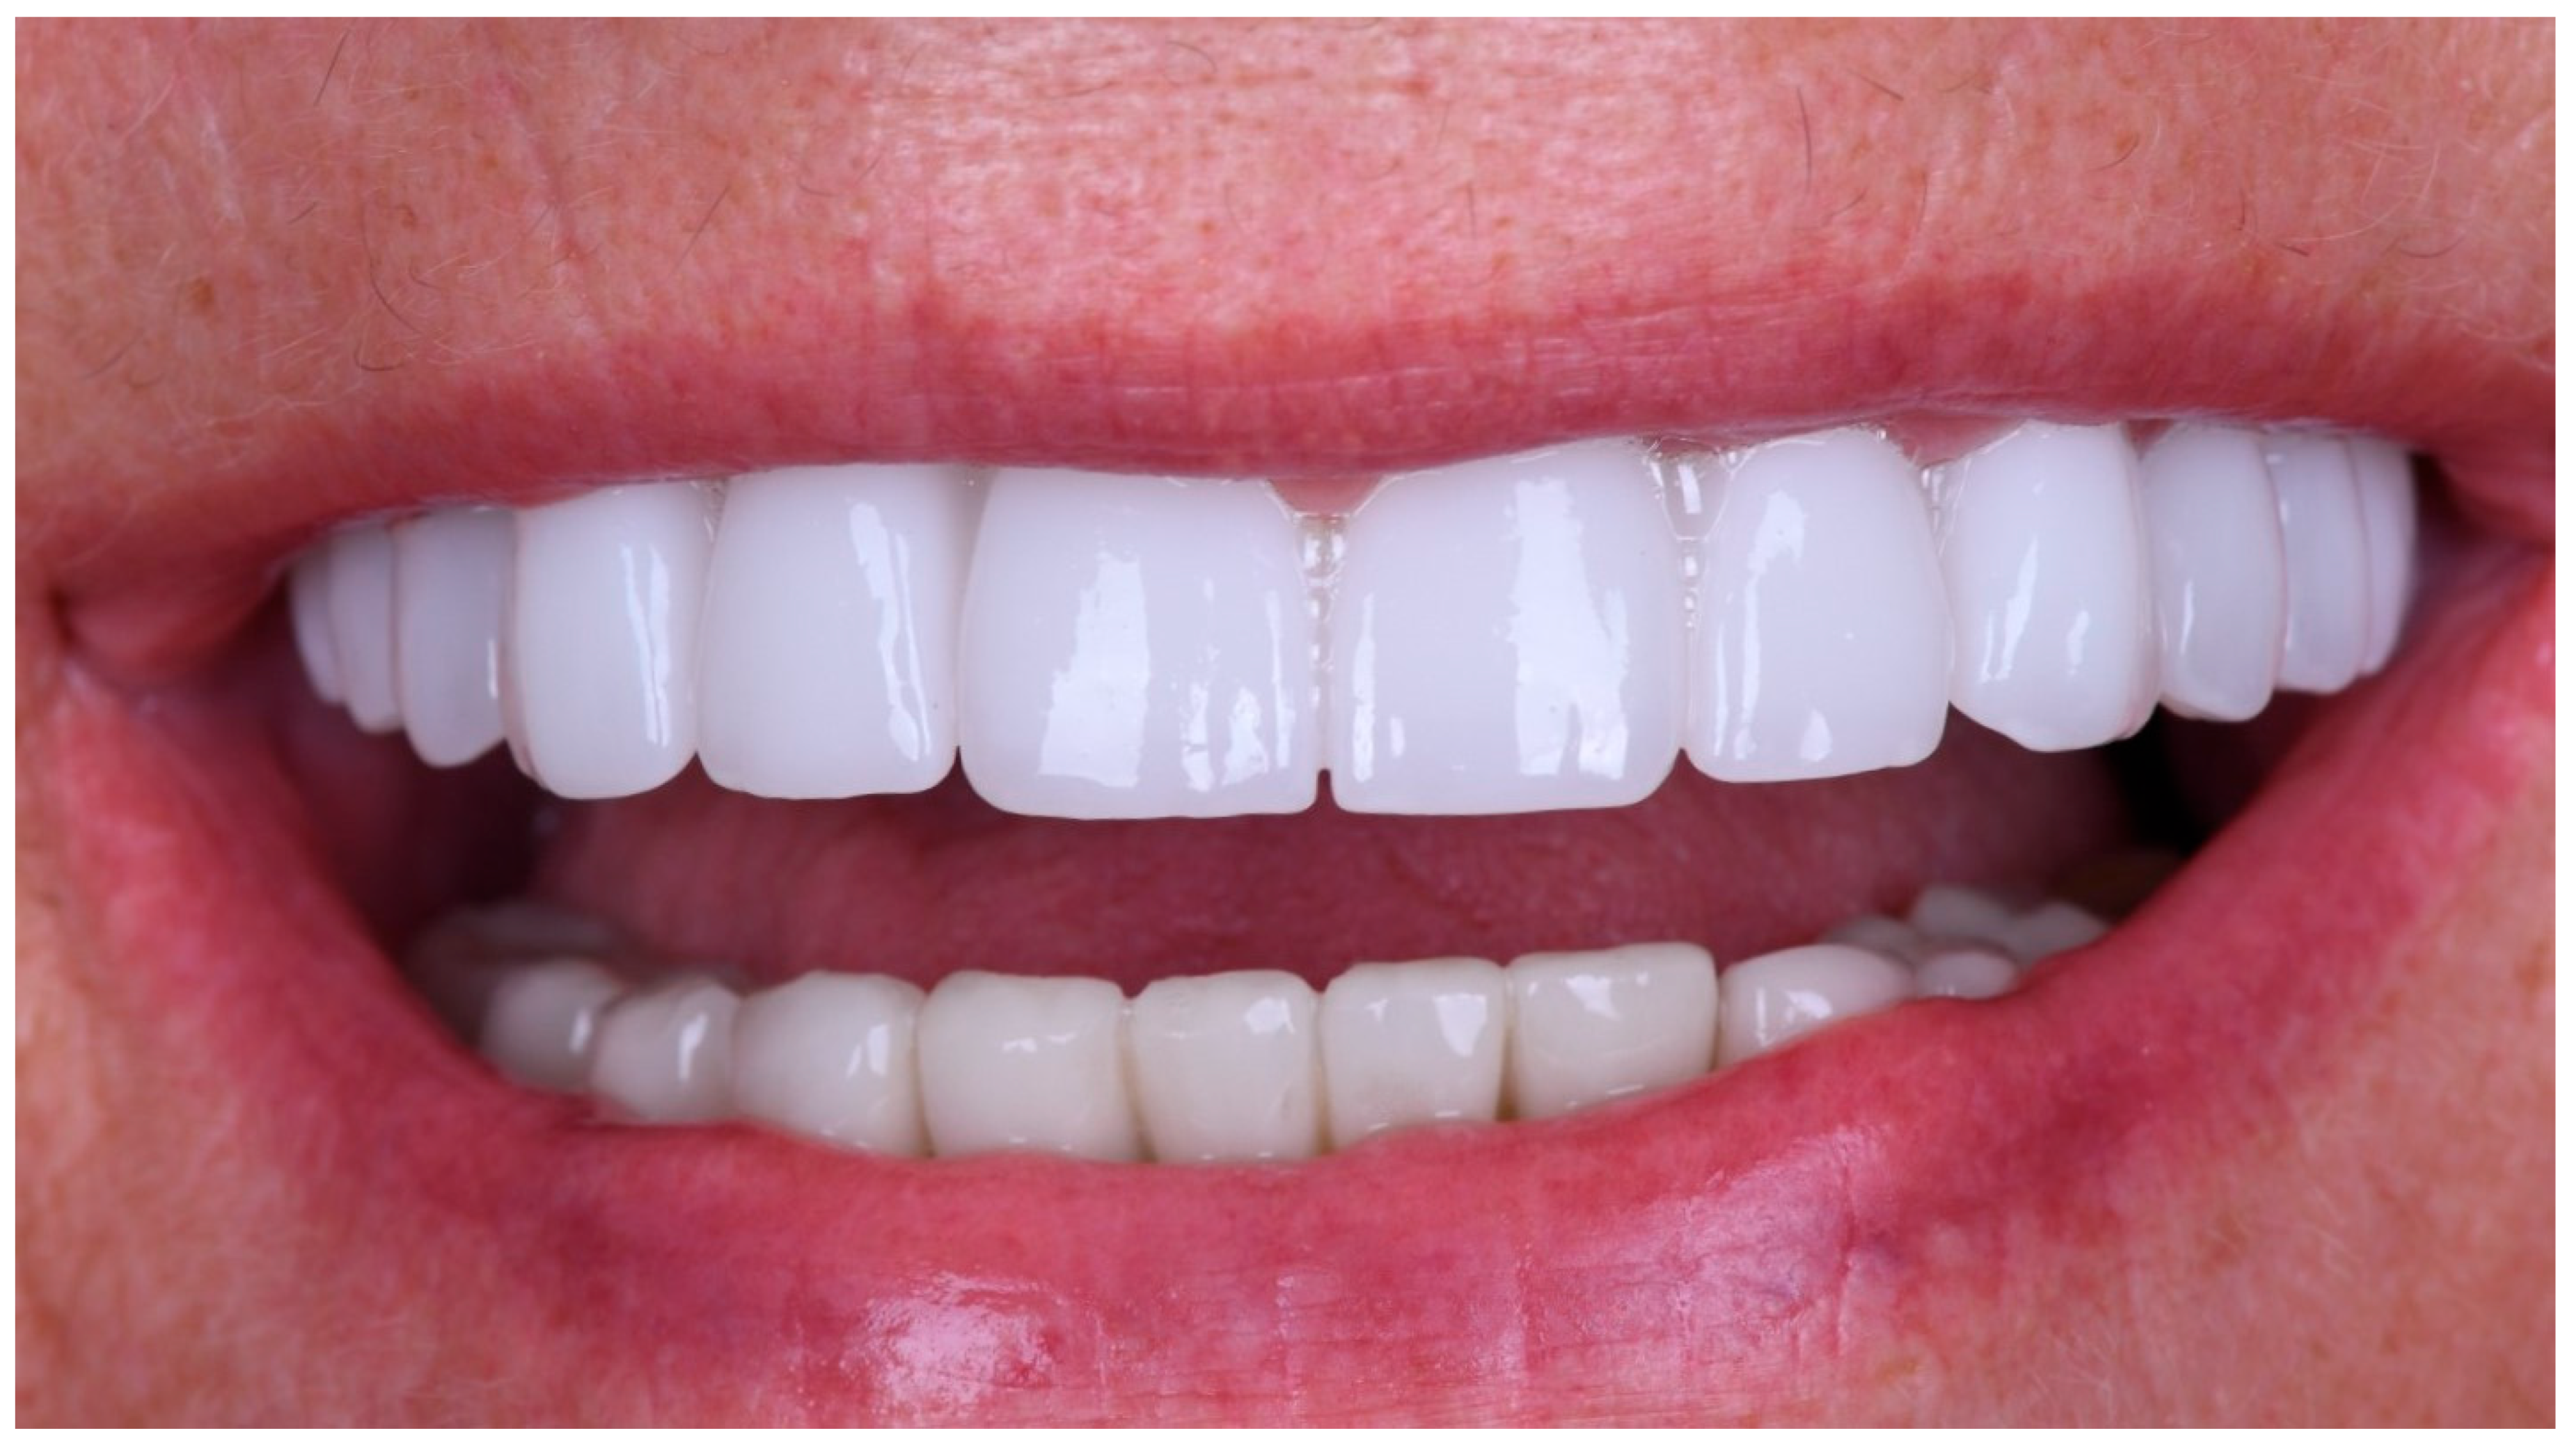

Following the confirmation of the passive fit, and a successful clinical try-in, the definitive full-arch prosthesis was fabricated as a monolithic zirconia superstructure on the same titanium framework (Figure 17) and delivered to the patient.

A custom-milled titanium framework provided rigidity and long-term stability. A monolithic full-contour zirconia superstructure was manufactured and bonded onto this framework, ensuring both mechanical strength and enhanced aesthetics. Recent reports confirm that zirconia-on-titanium combinations offer predictable outcomes in terms of aesthetics, function, and biological response [27].

The definitive prosthesis was delivered to the patient after laboratory verification. Intraoral evaluation confirmed accurate seating, passive fit, and proper occlusal relationships. Phonetics and aesthetics were reassessed and found to be satisfactory, consistent with previous retrospective data showing high survival rates and patient satisfaction with zirconia-based full-arch prostheses [28]. A panoramic radiograph was obtained at the time of prosthesis delivery to confirm the correct seating of the framework–zirconia assembly on all supporting implants, as well as to verify stable peri-implant bone conditions.

The restoration was torqued in line with the manufacturer’s specifications, and the screw access channels were sealed with composite resin. The definitive clinical situation in the patient’s mouth is shown in Figure 18 and Figure 19.

Static and dynamic occlusion were subsequently assessed using a digital OccluSense pressure analysis system (Bausch, Hainspitz, Germany).A follow-up was scheduled after 4 months, and the prosthesis demonstrated stable function and satisfactory aesthetics. The patient was fully satisfied.

At the 4-month follow-up, peri-implant tissues were clinically healthy, with no signs of inflammation or suppuration. Clinical and routine radiographic assessment performed during follow-up revealed no pathological findings. The patient reported high satisfaction with function and aesthetics. No biological, mechanical, or technical complications were observed during the follow-up period. The patient was also seen at a later recall visit, during which stable function and satisfactory aesthetics were maintained.

Figure 18. Extraoral frontal view of the definitive full-arch prosthesis in situ, demonstrating the final aesthetic outcome.

Figure 19. Extraoral smile view of the patient with the definitive restoration in situ.